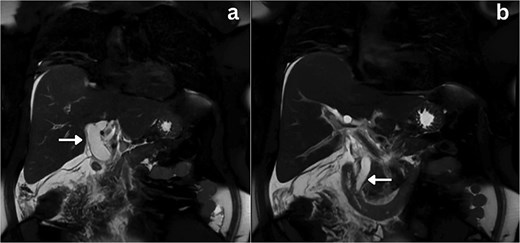

She was admitted, resuscitated, and started on intravenous antibiotics. Considering her previous history of cholecystectomy and deranged Liver Function Tests (LFTs), a clinical diagnosis of cholangitis was made. Magnetic retrograde cholangio-pancreatography (MRCP) was done, which showed significant dilatation of the biliary system extending down to the ampulla with the common hepatic duct (CHD) diameter of 23 mm with a normal pancreatic duct. Additionally, there was florid upper abdominal edema and fluid tracking along the right paracolic gutter (Fig. 1). There was no evidence of any common bile duct (CBD) stone or lesion to explain this dilatation. To further explore the underlying cause, a computed tomography (CT) pancreas was performed, which revealed no signs of pancreatitis nor any distal CBD or pancreatic lesions. The presence of fluid in the subhepatic and right paracolic regions likely indicated a bile leak (Fig. 2), but fluid related to pancreatitis could not be excluded. The findings were deliberated upon with the specialist hepatopancreaticobiliary (HPB) team and Specialist gastrointestinal (GI) radiologists. Despite extensive discussion and review with the radiologist, the nature of the fluid was not identified through the two imaging modalities employed. There was no obvious pancreatitis. A decision was reached to continue conservative management and opt for operative intervention in the event of clinical deterioration.

Coronal section MRCP imaging; a) Gross biliary dilatation (arrow), b) smooth tapering of the bile duct with no evidence of stones (arrow).